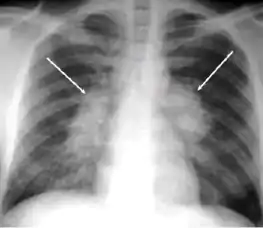

Chest X-ray of a person with advanced tuberculosis: Infection in both lungs is marked by white arrow-heads, and the formation of a cavity is marked by black arrows.

2. Any cavitary lesion - Lucency (darkened area) within the lung parenchyma, with or without irregular margins that might be surrounded by an area of airspace consolidation or infiltrates, or by nodular or fibrotic (reticular) densities, or both. The walls surrounding the lucent area can be thick or thin. Calcification can exist around a cavity.